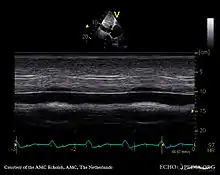

Echocardiography

If pulmonary hypertension is suspected based on the above assessments, echocardiography is performed as the next step.[12][15][56] A meta-analysis of Doppler echocardiography for predicting the results of right heart catheterization reported a sensitivity and specificity of 88% and 56%, respectively.[58] Thus, Doppler echocardiography can suggest the presence of pulmonary hypertension, but right heart catheterization (described below) remains the gold standard for diagnosis of PAH.[12][15] Echocardiography can also help to detect congenital heart disease as a cause of pulmonary hypertension.[12]